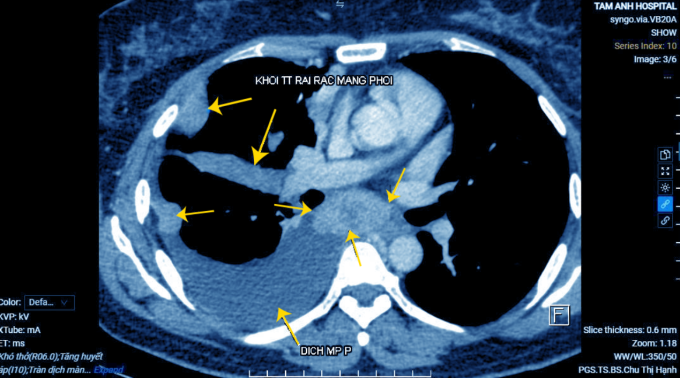

Bà Phương khó thở kèm đau tức ngực phải, ho khan kéo dài một tháng. Khám ở Canada ghi nhận bất thường nhưng qua nhiều tháng bà chưa đặt được lịch để bác sĩ chẩn đoán chuyên sâu, về Việt Nam đến Bệnh viện Đa khoa Tâm Anh Hà Nội khám. Kết quả chụp cắt lớp vi tính cho thấy tổn thương kích thước 3 cm ở thùy dưới phổi phải, xẹp thùy dưới phổi, tràn dịch màng phổi phải.

ThS.BS Nguyễn Văn Ngân, Khoa Hô hấp, Bệnh viện Đa khoa Tâm Anh Hà Nội, chọc hút dịch màng phổi kết hợp nội soi màng phổi nhằm quan sát tổn thương, lấy mẫu sinh thiết. Kết quả chọc hút được nhiều dịch màu vàng sẫm, có nhiều nốt và khối mọc dày đặc dưới màng phổi. Sinh thiết xác định bà Hương mắc bệnh ung thư phổi, di căn màng phổi. Hiện, người bệnh được điều trị theo phác đồ ung thư của bác sĩ, sức khỏe dần ổn định.